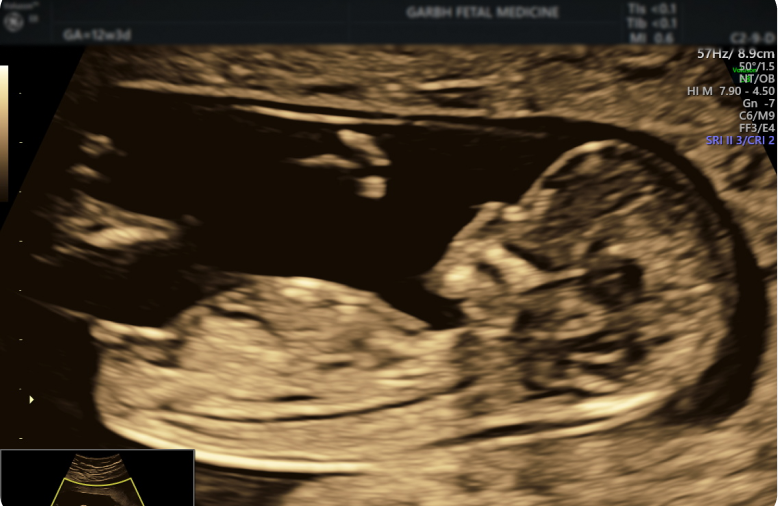

The NT scan is a non-invasive ultrasound test used to assess the risk of chromosomal abnormalities like Down syndrome. It measures the thickness of a fluid-filled space at the back of the baby’s neck (nuchal fold) and evaluates the nasal bone.

You may have heard the term NT NB scan and wondered how it is different from a regular NT scan. Both are the same. The “NB” stands for Nasal Bone. The presence of the baby’s nasal bone is always checked during an NT scan. This is another important marker during the first trimester.

In babies with certain conditions, such as Down syndrome, the nasal bone may be absent or underdeveloped at this early stage of pregnancy. Combining both, nuchal translucency and nasal bone assessment provides a more detailed picture of a baby’s development.

The NT scan is performed between 11 to 14 weeks of pregnancy. This is the optimal time for accurate measurement of nuchal translucency and proper assessment of chromosomal abnormality risks.